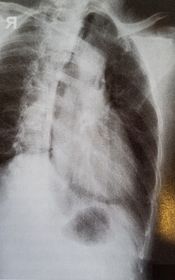

| PA Ribs Above Diaphragm Unilateral | patient rotated towards the right |

| PA Ribs Below Diaphragm Unilateral | Excessive obliquity |

| AP - LPO Ribs Above Diaphragm Unilateral | Insufficient obliquity |